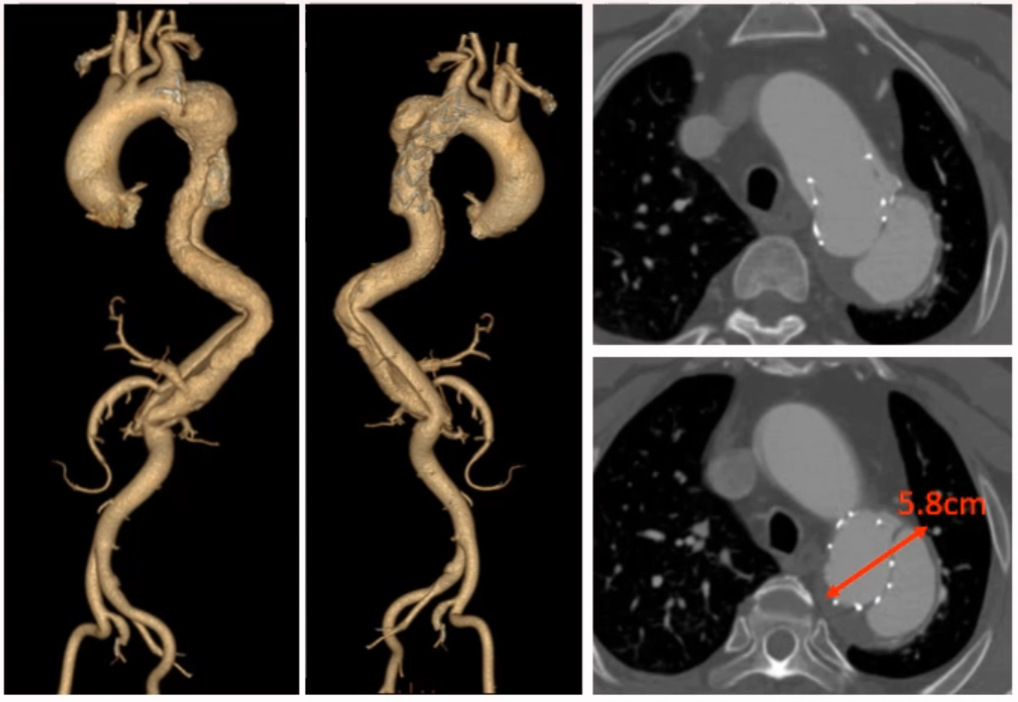

术前影像

术前CT呈现典型慢性夹层动脉瘤特征,近端有一枚支架,支架开口位于左锁骨下动脉开口以远,假腔内有造影剂,属于 Ia 型内漏;远端破口位于内脏动脉区,腹主动脉段无假腔,近端胸主动脉夹层动脉瘤最大直径 58 mm,手术指征明确。